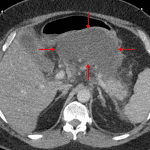

- Hypoenhancement of the pancreatic body as well as of portions of the head and tail

- Peripancreatic collection in lesser sac measuring 13 x 8 x 9 cm

- Adjacent mural thickening of the second and third portions of the duodenum

- Necrotizing pancreatitis

Acute necrotizing pancreatitis with an acute necrotic collection in the lesser sac, which should be more accessible to endoscopic rather than percutaneous drainage. No gas is identified within this collection.

No evidence of associated vascular complication.

Secondary duodenitis without evidence of obstruction.